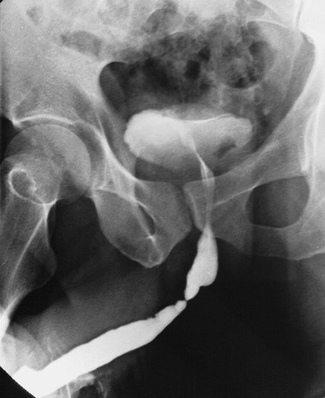

Фото: Травма уретры

• Ретроградная уретрография. Это один из наиболее точных методов диагностики. Контрастное вещество вводится в уретру и, при наличии проникающих травм, контраст распространяется в соседние ткани. Метод необходим перед катетеризацией уретры для определения степени повреждения. Для более полной информации метод может дополняться экскреторной урографией.